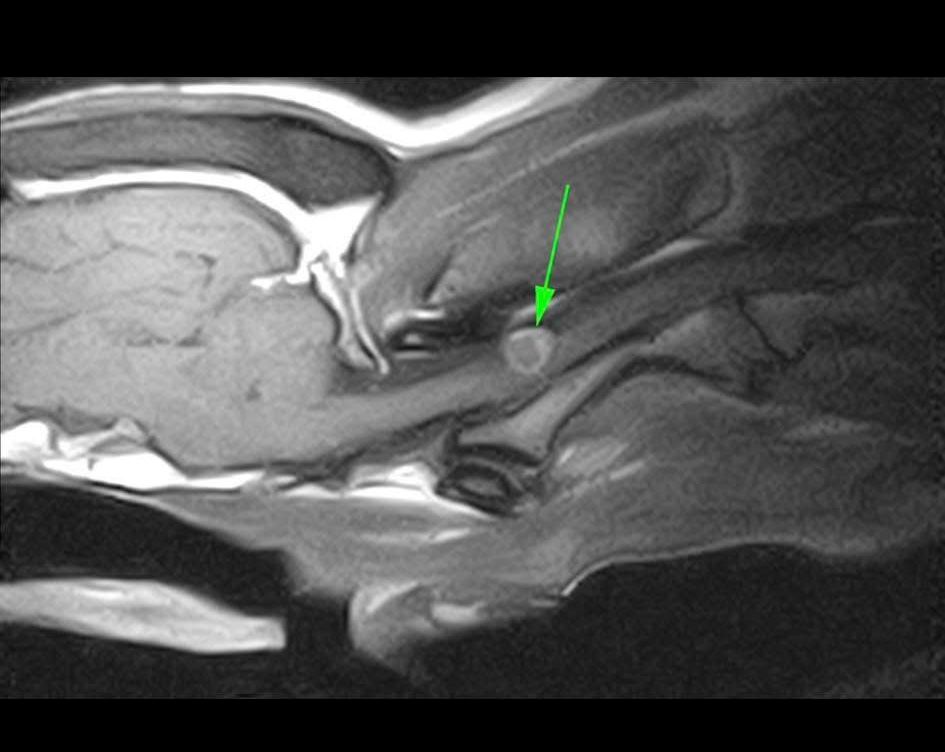

RISONANZA MAGNETICA